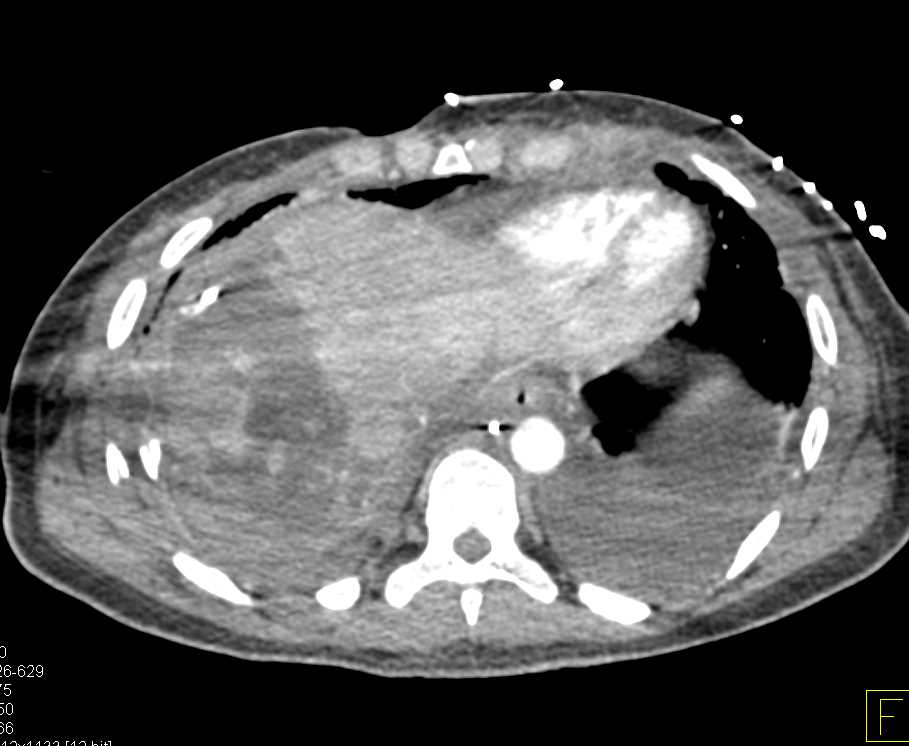

Metastastic Renal Cell carcinoma to the Right Adrenal